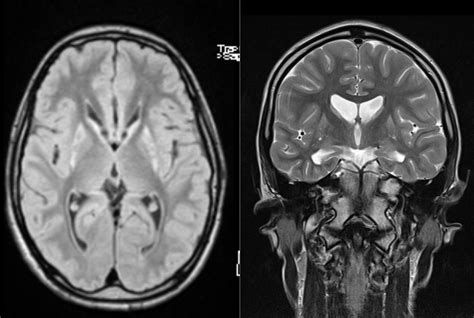

So, what’s the deal with Huntington’s Disease (HD), really? At its core, HD is a progressive neurodegenerative disorder – that’s a fancy way of saying it’s a condition where brain cells gradually break down and die over time. This breakdown leads to problems with movement, thinking, and psychiatric issues, which is why some might mistakenly think of it as “three diseases in one” – it truly is a comprehensive challenge to the entire person. Unlike some other neurological conditions, Huntington’s Disease is inherited , meaning it’s passed down through families. If one of your parents has the gene that causes HD, you have a 50% chance of inheriting it yourself. It doesn’t skip generations, guys; if you have the gene, you’ll eventually develop the disease. Most people start showing symptoms in their 30s or 40s, but it can hit earlier (juvenile HD) or later (late-onset HD), making its timing incredibly unpredictable and often devastating for families. The gene responsible for HD is called the HTT gene, and it’s located on chromosome 4. A specific mutation in this gene, an expanded CAG trinucleotide repeat, is the culprit. When this repeat sequence gets too long, it produces an abnormal protein called huntingtin , which is toxic to certain brain cells, particularly in areas like the basal ganglia, crucial for movement control, and the cortex, vital for thinking and emotion. As these critical brain cells deteriorate, the person’s abilities slowly but surely decline. This isn’t just a physical battle; it’s a mental and emotional one, too, making comprehensive support absolutely vital for anyone living with Huntington’s Disease and their families. Understanding this fundamental genetic cause is the first step in appreciating the complexities and the challenges faced by those affected, emphasizing why early diagnosis and ongoing support are so crucial.